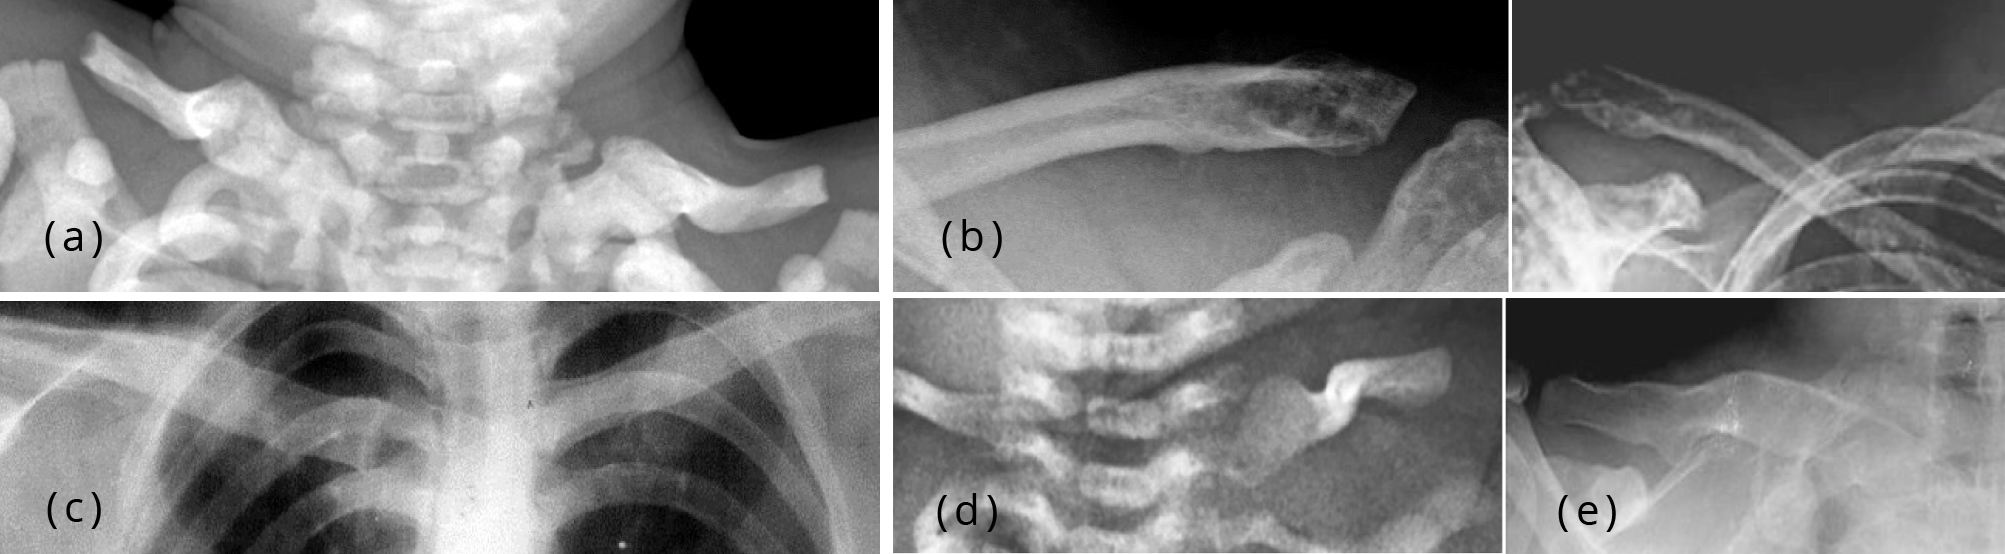

Radiographic images of a 10yearold male with Pyle disease. A, B Pyle S Disease A rare bone dysplasia characterized by long bones with wide and expanded metaphyses, thin cortical bone and bone fragility. Pyle disease is a rare bone disorder characterized by long bones with wide metaphyses, thin cortical bone, and bone fragility leading to fractures. Pyle disease is a disorder of the bones. Pyle's disease, also known as metaphyseal dysplasia, is a rare. Pyle S Disease.